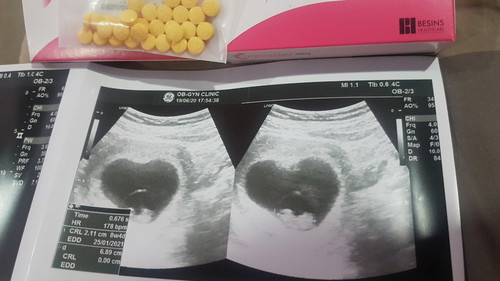

หลังจากได้เจอหมอใจเราก็ชื่นมาหน่อยหมอเห็นน้องแล้วค่ะ9wแต่ยังต้องกินยาเพิ่มฮอร์โมนกับยากันแท้งต่อไปให้อายุครรภ์ได้14-15wกันเลยเพราะแม่เคยแท้งมา2ท้องติดกันท้องนี้ต้องดูแลดีกว่าเดิมและระวังให้มากกว่าเดิมค่ะ เพิ่มเติมอีแม่เปลี่ยนหมอดูแลด้วยจ้า

หม่าม๊า of 2 สุดน่ารัก เจ้าชาย